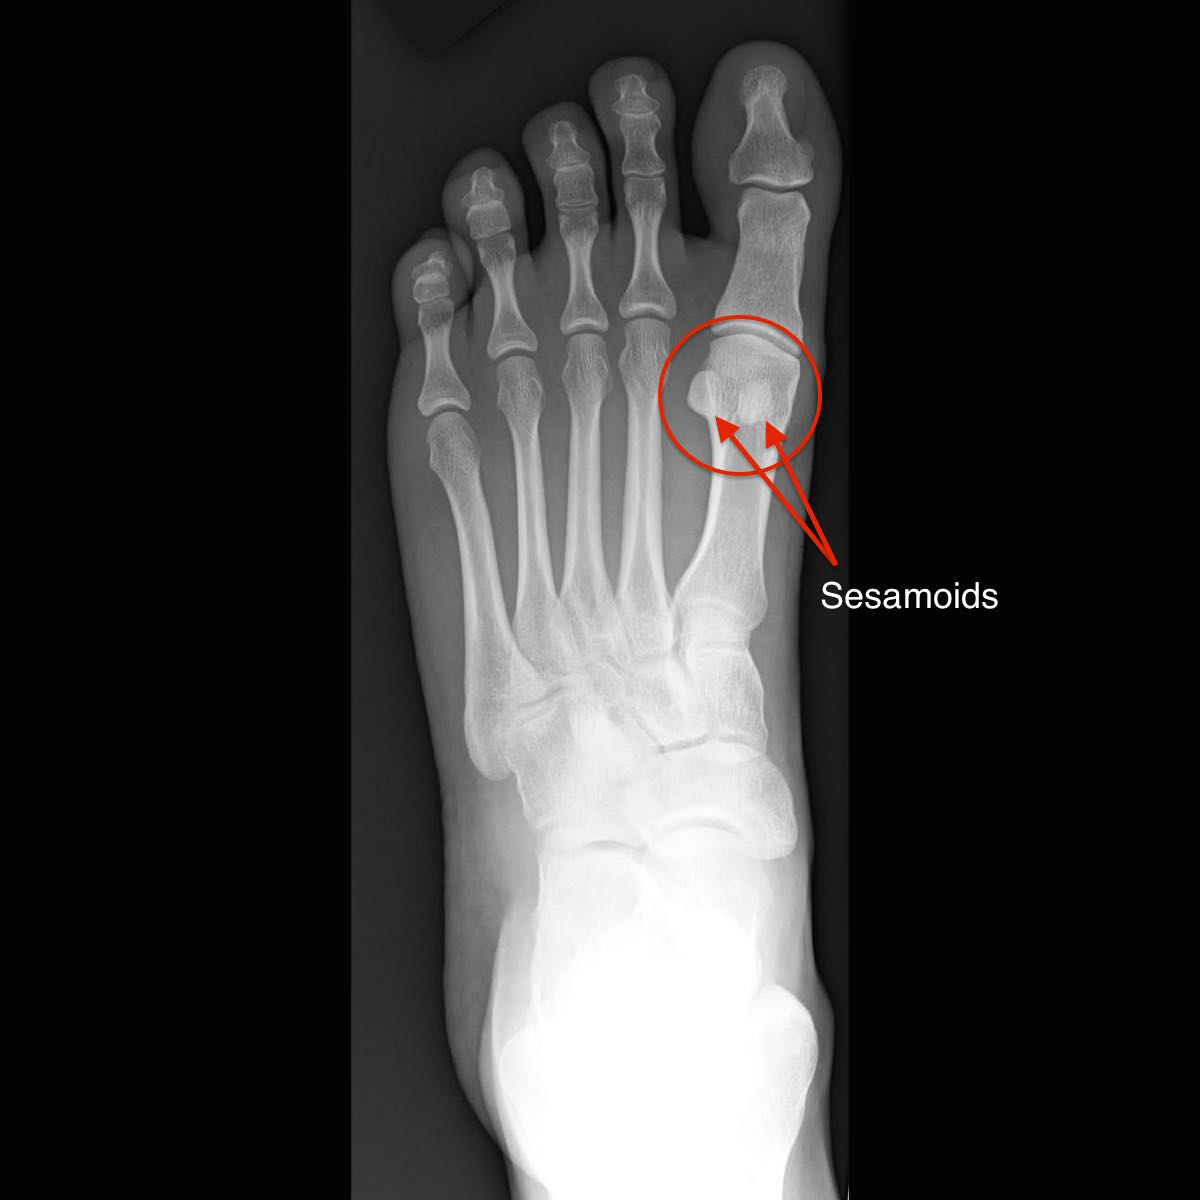

Sesamoiditis is inflammation of one of two small, egg-shaped bones about the size of a peanut M&M candy sitting under the big toe joint. The sesamoids are found in every foot, and can appear as complete bones, or can form after birth in two or three separate pieces. They provide an assisting role in bearing weight across the big toe joint and stabilize the various structures that cross over and around the big toe joint. Injury to these bones can happen on an acute and chronic basis.

Sesamoiditis is diagnosed during a simple foot exam, although x-rays are often used to rule out a stress fracture or true fracture of the bone. Stress fractures of the sesamoids can mimic the symptoms of sesamoiditis, and may be difficult to diagnose properly as they may not show up early on the x-ray. MRI may be needed to rule a stress fracture out.